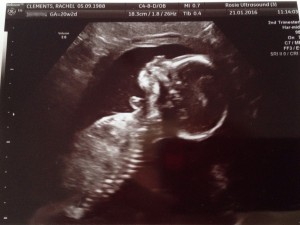

I was astonished at just how in-depth the ultrasound was with the detailing it was able to pick-up despite bubba only being roughly 6.5 inches at the time. From the structures of his/her brain, to the layers of the spine, to the emptying of the bladder, and the development of the tiny feet…everything was perfect. Finally, the remaining organs that needed to be checked-over were the kidneys; the right one was visible almost immediately, but after 20 minutes of searching, it appeared there was no left kidney and a large fluid/cystic mass was located next to the bladder.